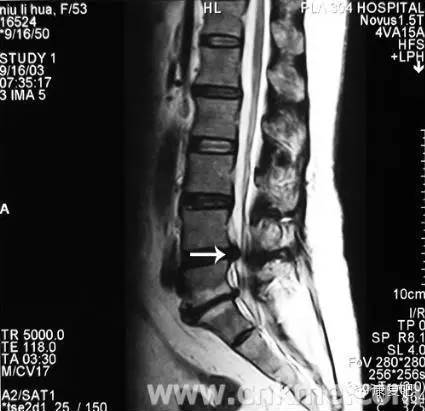

3、核磁共振攝影(MRI)

可顯示出狹窄的部位(脊髓腔的狹窄)、椎間盤物質(zhì)的突出進入脊髓腔、或受侵害之脊髓神經(jīng)根。